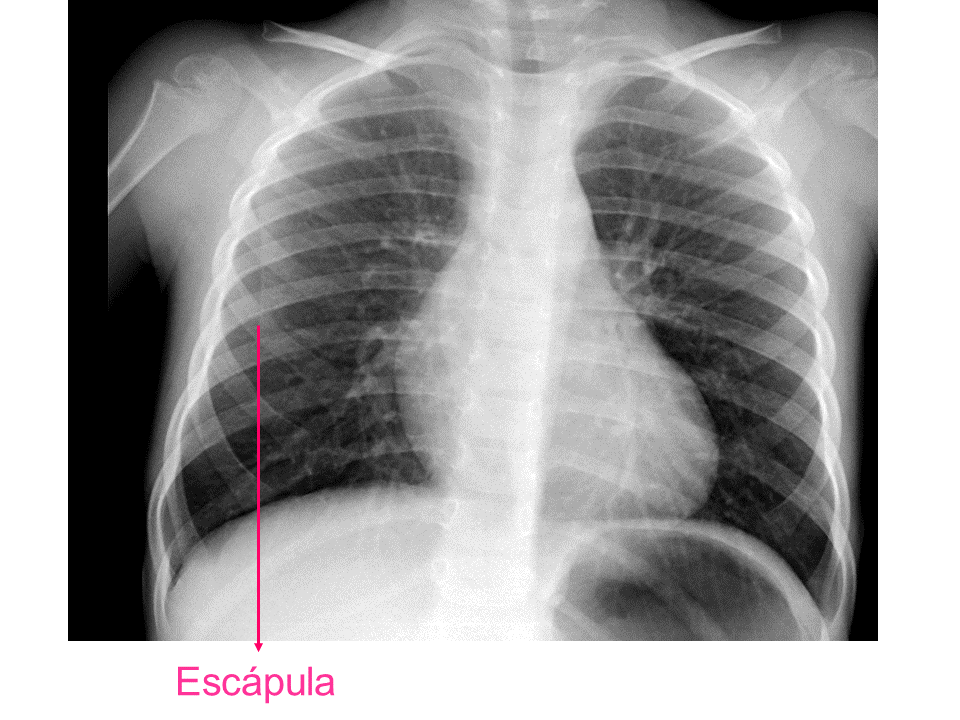

Para una adecuada lectura sistemática de la radiografía de tórax, debemos conocer la anatomía radiológica básica e identificar determinadas estructuras2.

• Escápula